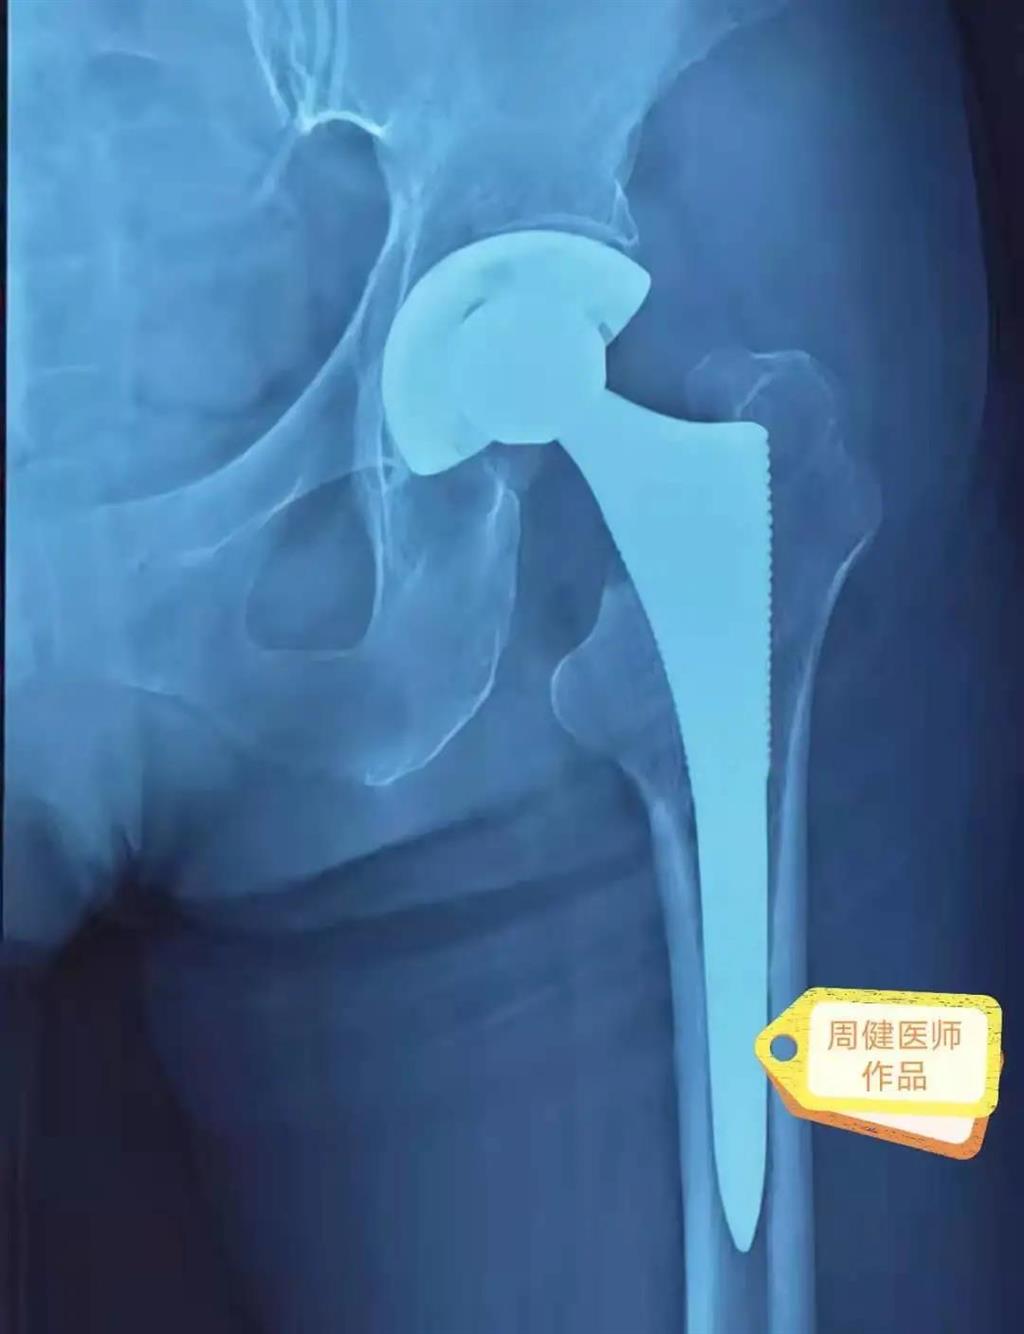

6月30日的“關(guān)節(jié)置換術(shù)”,患者是一位上了年紀(jì)的老人,苦于病痛折磨多年的他四處“求醫(yī)問藥”,最后在多位專家醫(yī)師及病友地力薦下選擇了和平國際醫(yī)院,在醫(yī)師團(tuán)隊(duì)“偷天換日”般的手術(shù)后,老人成功告別了苦纏多年的病痛。

周健說,這場“關(guān)節(jié)置換術(shù)”對(duì)于他們團(tuán)隊(duì)而言其實(shí)算是比較普通的手術(shù),因?yàn)樽鲞^很多同類的手術(shù),成功案例繁多,因此在手術(shù)操作上有較多地實(shí)操經(jīng)驗(yàn)。“不過話雖如此,作為醫(yī)生我們對(duì)于每一場手術(shù)都會(huì)全力以赴,這是為醫(yī)者的職責(zé)也是義務(wù)。”